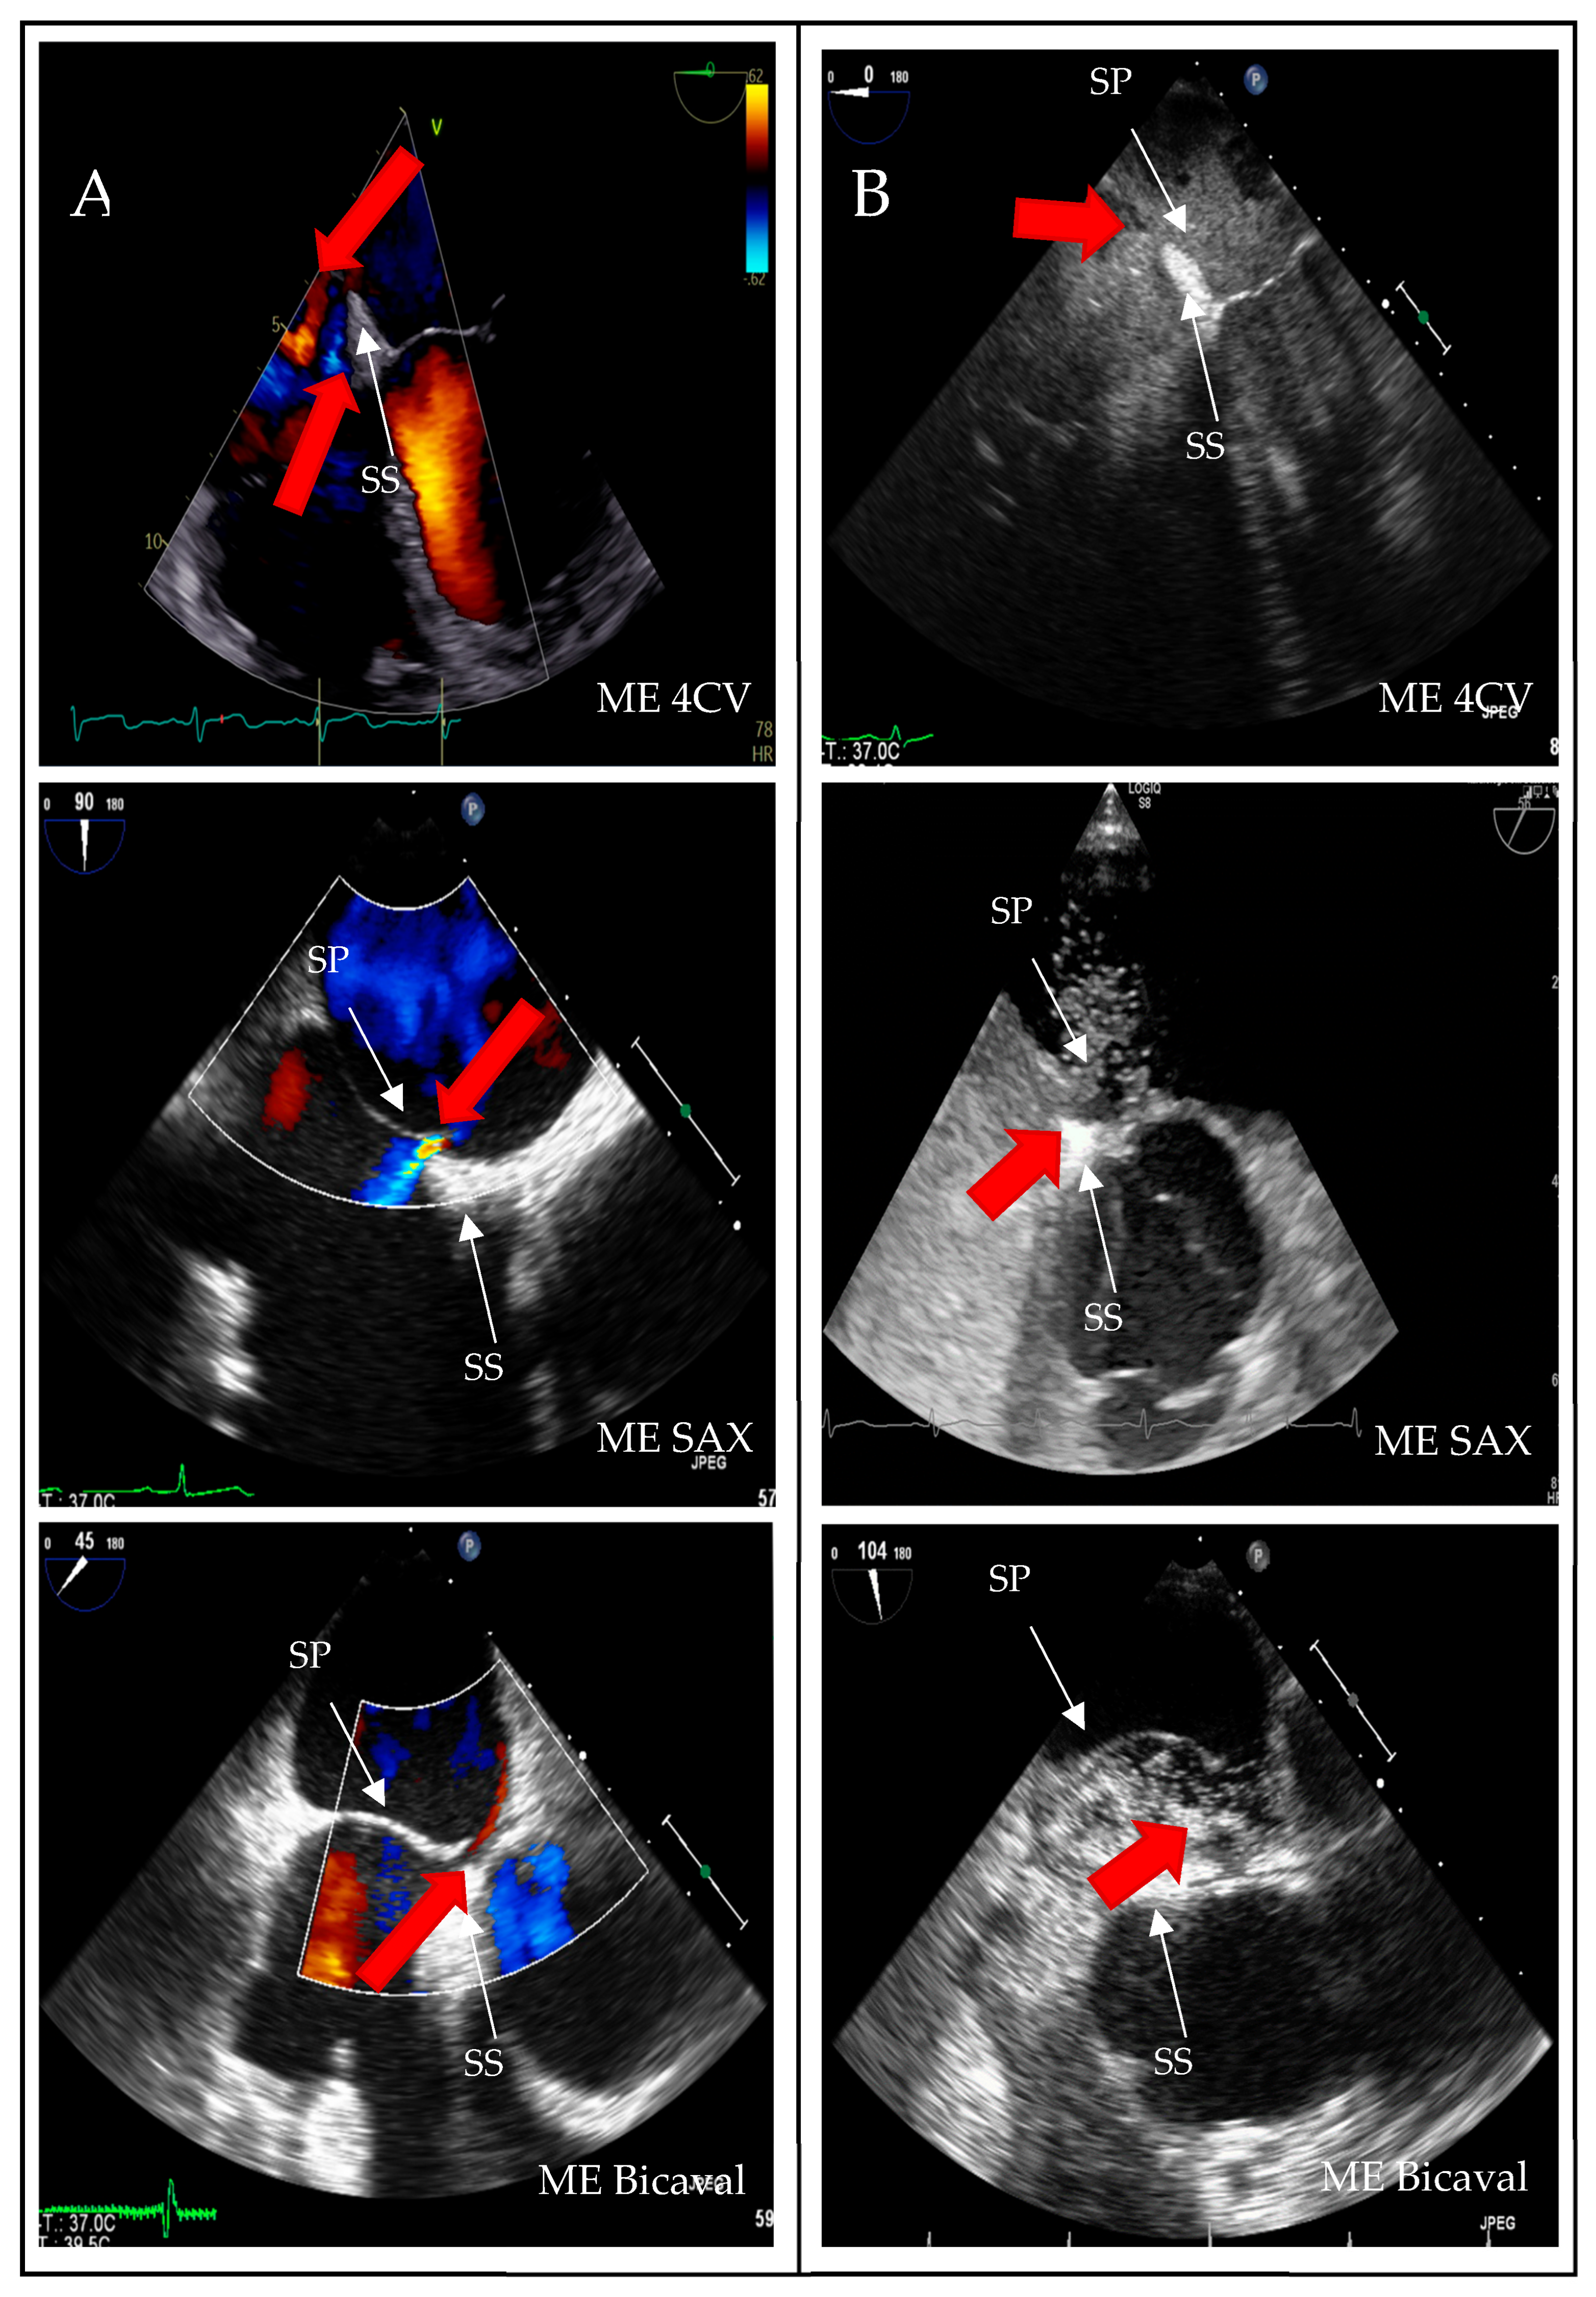

A structured approach could transform PFO diagnosis from a highly operator-dependent procedure into a reproducible, high-quality standard, particularly beneficial for less experienced operators. Given the results presented, we investigated whether precise quality indicators could enhance the reliability of PFO diagnosis in the context of transesophageal echocardiography (TEE). Standard TEE views demonstrating PFO shunting are shown in Figure 3.

Figure 3. Two-dimensional TOE recordings of an IAS with PFO. Shown is a short circuit between the RA and LA in ME 4CV, ME SAX, ME Bicaval image planes (A) in the color Doppler and (B) in the bubbles test; the red arrow indicates the direction of the short circuit. ME: midesophageal, SAX: short axis, 4CV: four chamber view, SP: septum primum, SS: septum secundum.

The PFO is situated in the anterior–superior part of the fossa ovalis [3]. Visualization of the anterior fossa ovalis limb on TEE is typically achieved only in the short axis at the level of the aortic valve (mid-esophageal aortic valve short axis view, ME AV SAX). However, statistical analysis showed no significant correlation between this probe position and diagnostic accuracy (p = 0.21; odds ratio [OR] 2.99). In contrast, the mid-esophageal bicaval view (ME Bicaval) demonstrated a strong correlation with accurate diagnoses (p < 0.001; OR 5.23), as it presents the superior aspect of the fossa ovalis where the PFO is located [3]. Additionally, the four-chamber view was found to be statistically significant (p = 0.04; OR 1.12); however, its relevance in PFO diagnostics is questionable as it primarily images the posterior region of the fossa ovalis limbus, which is less important for PFO identification.

The finding from our multivariable analysis that the mid-esophageal bicaval view is an independent predictor of accurate diagnosis is particularly significant. It underscores the critical role of specific imaging planes in revealing the anterior–superior location of the PFO, an area often not fully visualized in standard four-chamber or short-axis views. This highlights the importance of a structured, comprehensive approach to TEE rather than relying on a single, frequently-used view. These results suggest that while operator experience is crucial, its impact can be enhanced by strict adherence to a standardized checklist of views, particularly in the setting of ambiguous findings, as this reduces the risk of diagnostic errors stemming from incomplete anatomical assessment.

The strongest predictor of accurate diagnosis was the consistent use of the mid-esophageal bicaval view, which directly visualizes the anterosuperior portion of the fossa ovalis. Reliance on a single frequently used view, such as the aortic valve short axis, was insufficient and contributed to false-positive PFO diagnosis. These findings support the implementation of structured checklists incorporating key probe positions and bubble test execution, thereby reducing operator dependence.